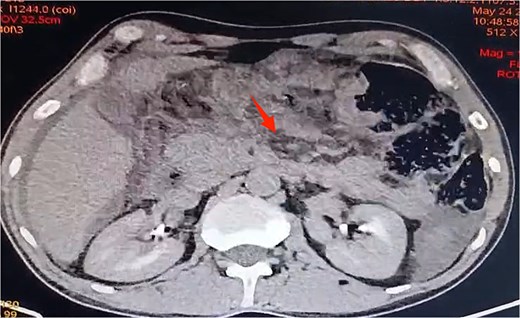

A contrast-enhanced abdominal CT showed Balthazar E pancreatitis with peripancreatic necrosis, thickening of the transverse colon and first jejunal loop, and sealed colonic perforation. Perisplenic and perihepatic fluid collections were noted, with no free air (Figs 1 and 2).

Axial view of contrast-enhanced abdominal CT scan revealing Balthazar E pancreatitis with peripancreatic necrosis.